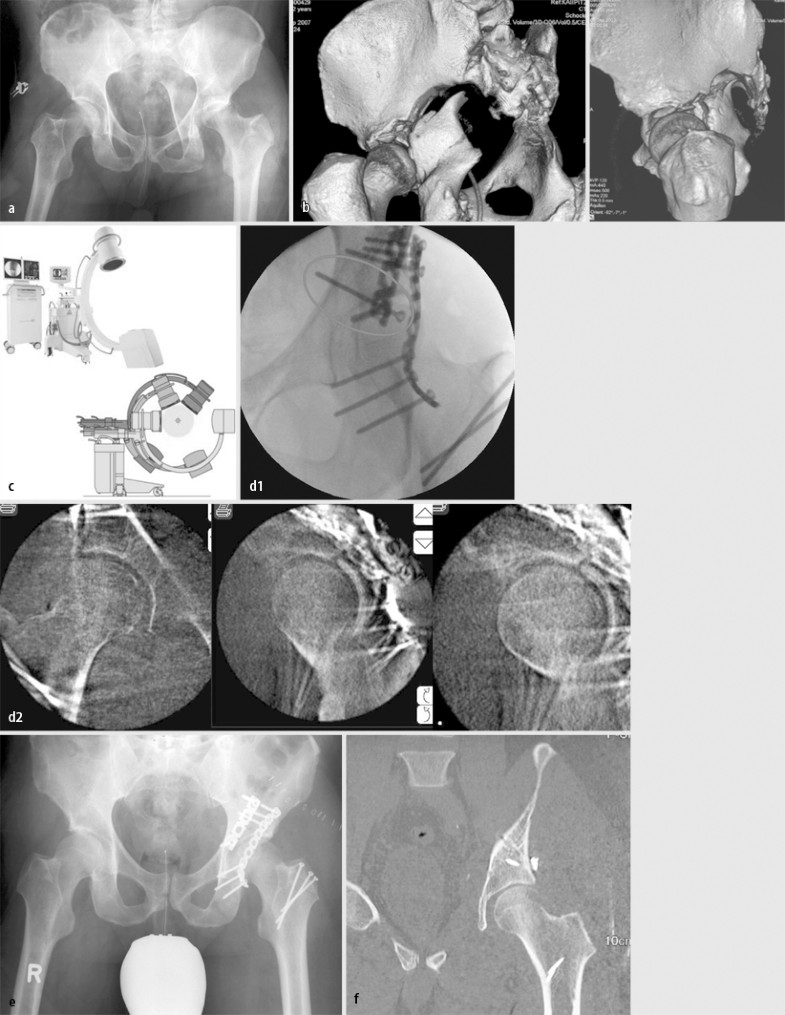

Frakturen des Beckenrings und des Azetabulums treten selten isoliert auf. Bei mehr als der Hälfte der Patienten finden sich zusätzliche Brüche [5, 7], der Anteil Polytraumatisierter beträgt bis über 30% [2, 7]. Ist die Verletzung der Beckenregion klinisch besonders augenfällig und unterbleibt eine systematische Suche nach weiteren Verletzungen entsprechend dem Polytraumaalgorithmus, kann eine relevante Begleitverletzung primär übersehen werden (Abb. 5). Somit sollte prinzipiell gerade beim Rasanztrauma von „okkulten“ Begleitverletzungen ausgegangen und danach gefahndet werden.

Fall 5, 50-jährige Polytraumapatientin (AO 61C1.2), a,b Symphysensprengung und transiliosakrale Luxationsfraktur rechts, c gleichzeitige B-Verletzung der Wirbelsäule BWK12/LWK, d dorsoventrale mehrsegmentale Stabilisation, e ORIF der Beckenringfraktur, weitere Erläuterungen s. Kasuistik

Fall 5

Bei der 50-jährigen Polytraumapatientin mit bekanntem Morbus Bechterew lagen eine AO-Verletzung 61C1.2 mit Symphysensprengung und transiliosakraler Luxationsfraktur rechts sowie gleichzeitig eine B-Verletzung der Wirbelsäule BWK12/LWK1 ohne neurologisches Defizit vor.

Die Versorgung erfolgte durch dorsoventrale mehrsegmentale Stabilisation sowie ORIF der Beckenringfraktur (Abb. 5).